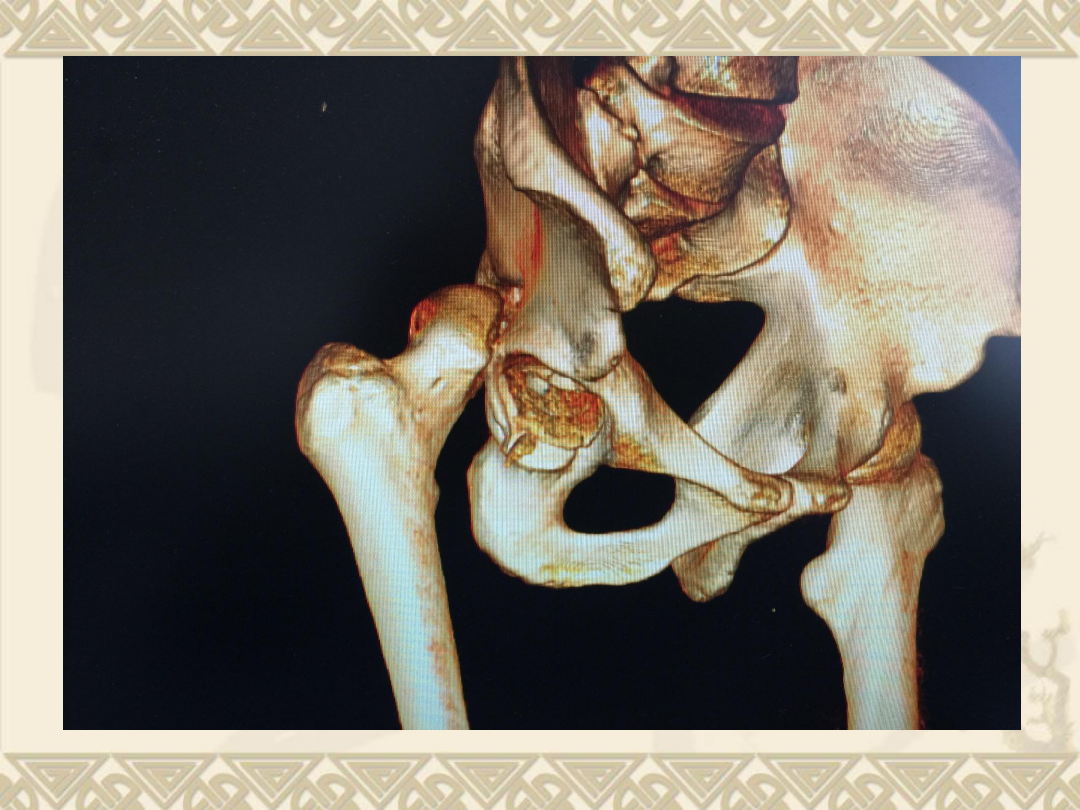

CT

v

、右股骨头骨折(

Pipkin

Ⅳ型骨折)

2

、髋关节后脱位

3

、髋臼后缘骨折